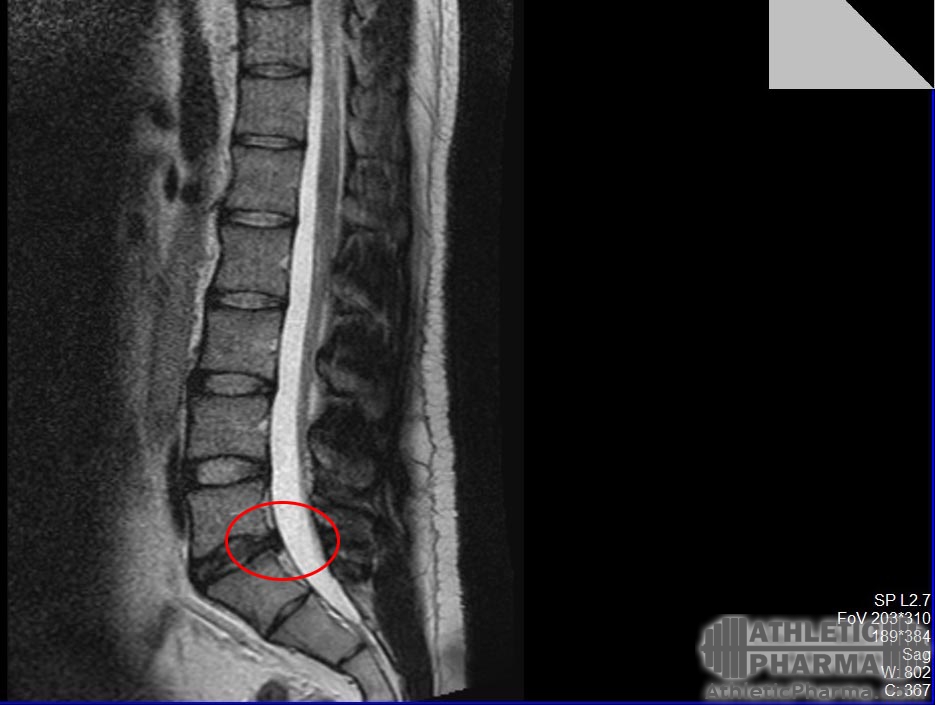

2011 грыжа межпозвоночная